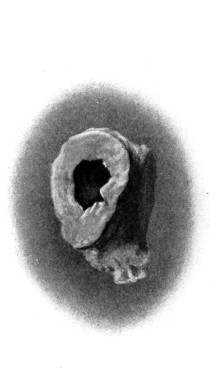

| 40 and 41. To show the relation of basic fractures to the petrous bone | 104, 105 |

| 42. A comminuted fracture of the skull | 112 |